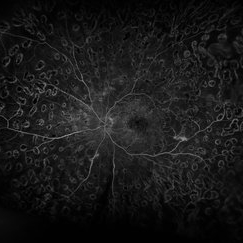

Central Retinal Vein Occlusion with Severe Ischemia

Composite fluorescein angiogram of the left eye of a male with a Central Retinal Vein Occlusion with severe ischemia.

Photographer: Olivia Rainey

Imaging device: Heidelberg Spectralis

Condition/keywords: central retinal vein occlusion (CRVO), composite, fluorescein leakage, ischemic CRVO